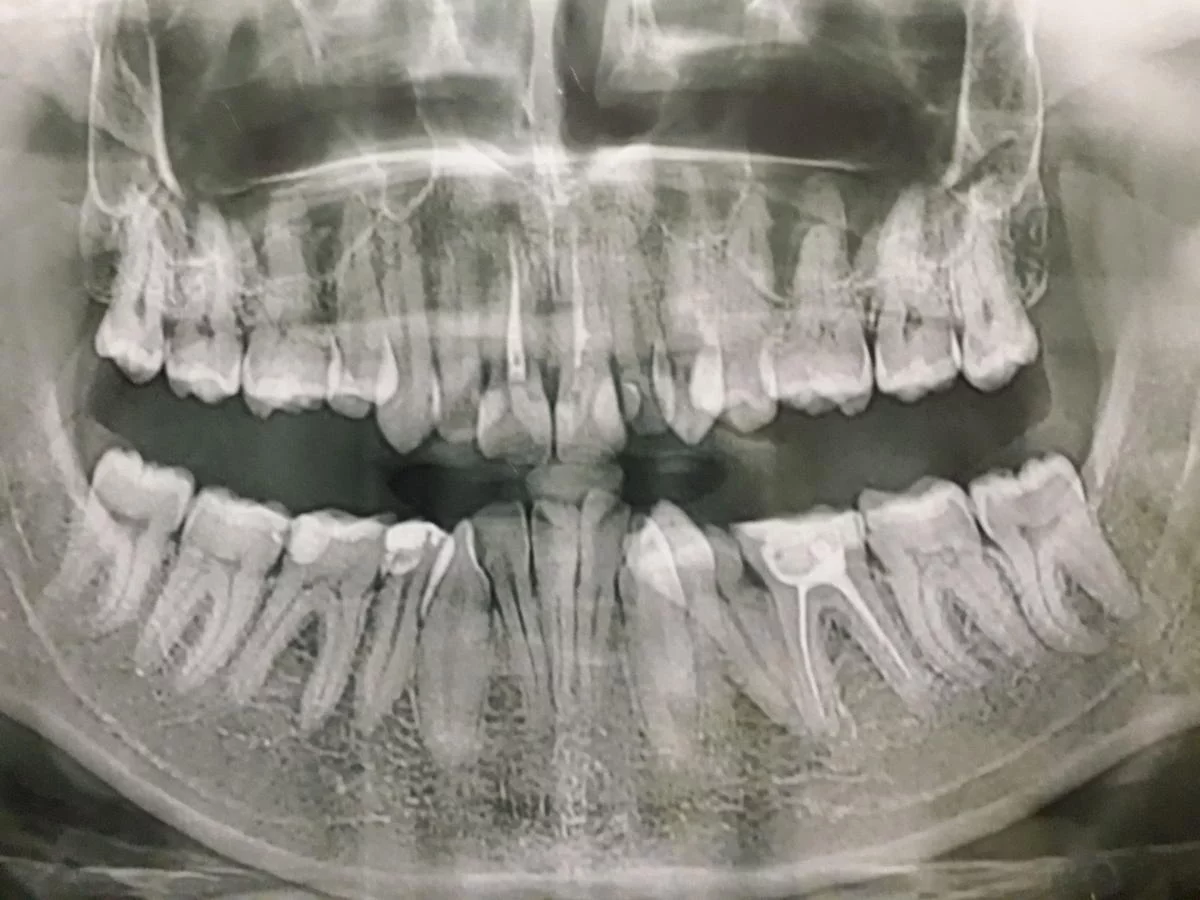

Здравствуйте, уважаемые врачи. Родственник насобирал к 25 годам немного денег и хотел бы исправить ужас во рту. Подскажите, на сколько, по вашему мнению, это реально в такой печальной ситуации, какие "подготовительные работы" на ваш взгляд нужно провести перед установкой брекетов - интересует, в частности, удаление 8-к и т.д. прикус неправильный, верхняя челюсть почти-полностью накрывает нижнюю. Может, посоветуете конкретные системы коррекции. Заранее большое спасибо.

п.с. если кто-то порекомендует опытного толкового врача, который бы взялся и не драл три шкуры, буду очень благодарна.

Вкладення

• .webp

.webp

74.3 КБ · Перегляди: 689